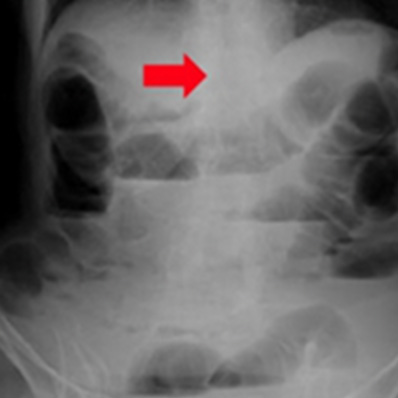

イレウス

両腎結石症